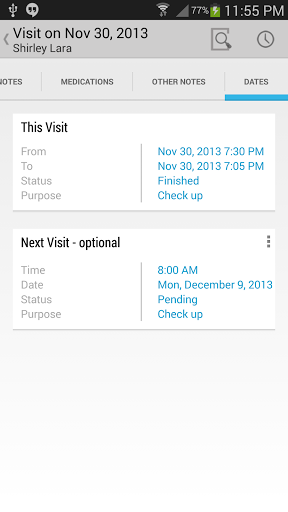

• Voir la visite du patient / antécédents médicaux

• Pendant les visites des patients, ajouter des notes de visite / médicales comme du texte, une image, un enregistrement vocal ou une écriture manuscrite

• Exporter un rendez-vous vers le calendrier android